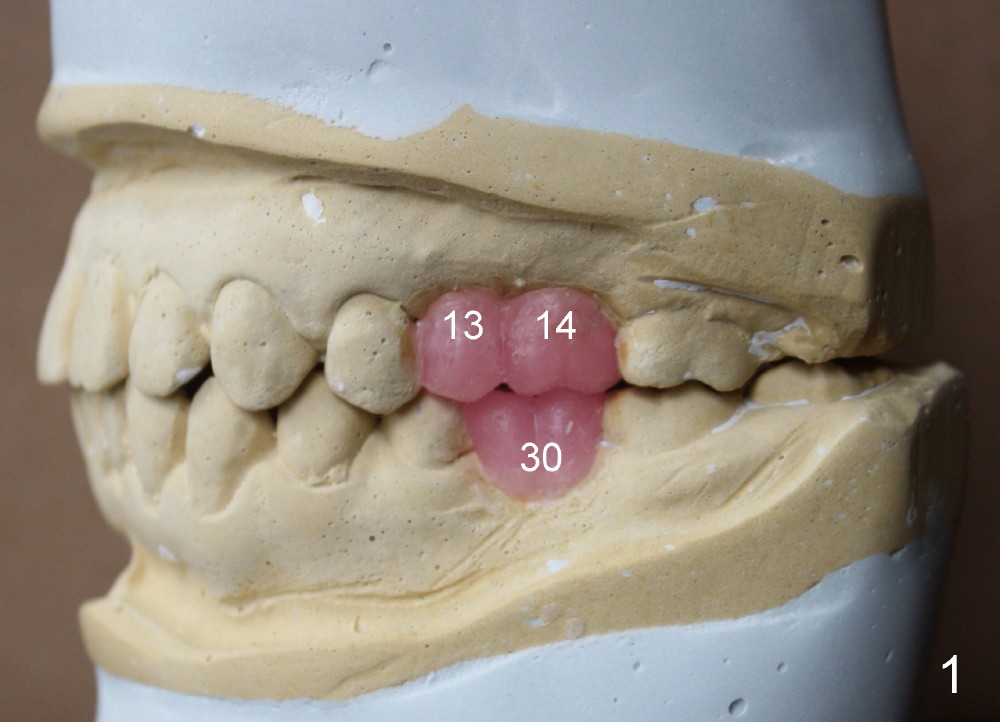

Bone height is limited for implant placement at the sites of the 2nd premolar and the 1st molar (Fig.3: #13,14), 7.68 and 4.45 mm, respectively (Fig.4).  The depth of the pilot drills is controlled between 6 and 8 mm for #13 and less than 6 mm for #14 at the crest.

Bone expanders are used to form osteotomy and internal sinus lift if bone density is found to be low on pilot drilling.  Expanders are used until 3.0 or 3.4 mm for #13 and 3.8 or 4.3 mm for #14.  A perio or implant explorer is used to check integrity of the apex of the osteotomy.  Allograft and Osteogen will be used for sinus lift.

A 4x14 and 5x11 mm one-piece implants will be used (Fig.4; apices being pointed (red lines); while abutments being attached (pink lines)).  Approximately 4-5 mm implants will stick into the sinus space (but underneath the sinus membrane).  Immediate provisionals are to be splinted without any occlusal contact.